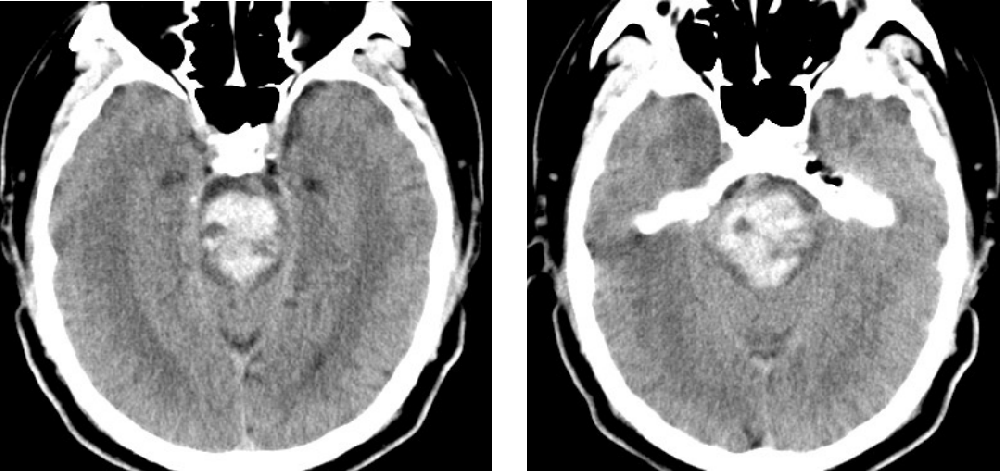

患者,男,45歲,1月2日因“突發(fā)昏迷1小時”被同事送至我院,急診CT檢查示腦干大量出血,出血量約15ml。此時患者已深度昏迷,各項生理反射消失,自主呼吸不穩(wěn)定,肢體強直并出現(xiàn)中樞性高熱,體溫40℃。因病情危重、隨時可能出現(xiàn)呼吸心跳驟停,緊急收入重癥監(jiān)護室,給予氣管插管、呼吸機通氣,維持各項生命指標(biāo)治療。

在手術(shù)室、麻醉科的積極配合下,整個手術(shù)團隊分工有序、緊密配合,采用顳下入路,切開小腦幕,暴露并保護滑車神經(jīng)、三叉神經(jīng)、大腦后動脈,應(yīng)用顯微鏡在橋腦三叉神經(jīng)上區(qū)域通過4毫米的通道,清除腦干內(nèi)10余毫升出血,并對原發(fā)出血部位妥善止血。經(jīng)過3個多小時的精細操作,在確保最小腦損傷的情況下清除血腫,術(shù)中各項監(jiān)測指標(biāo)平穩(wěn),術(shù)后復(fù)查頭顱CT顯示血腫清除滿意。術(shù)后經(jīng)過重癥監(jiān)護室積極治療,患者平穩(wěn)渡過中樞性高熱、嚴重肺部感染、營養(yǎng)低下等并發(fā)癥期,各項生命體征逐步平穩(wěn),對外界刺激有適當(dāng)反應(yīng),術(shù)后13天轉(zhuǎn)入普通病房繼續(xù)康復(fù)促醒治療。

附手術(shù)前患者顱腦CT:

術(shù)后患者顱腦CT: